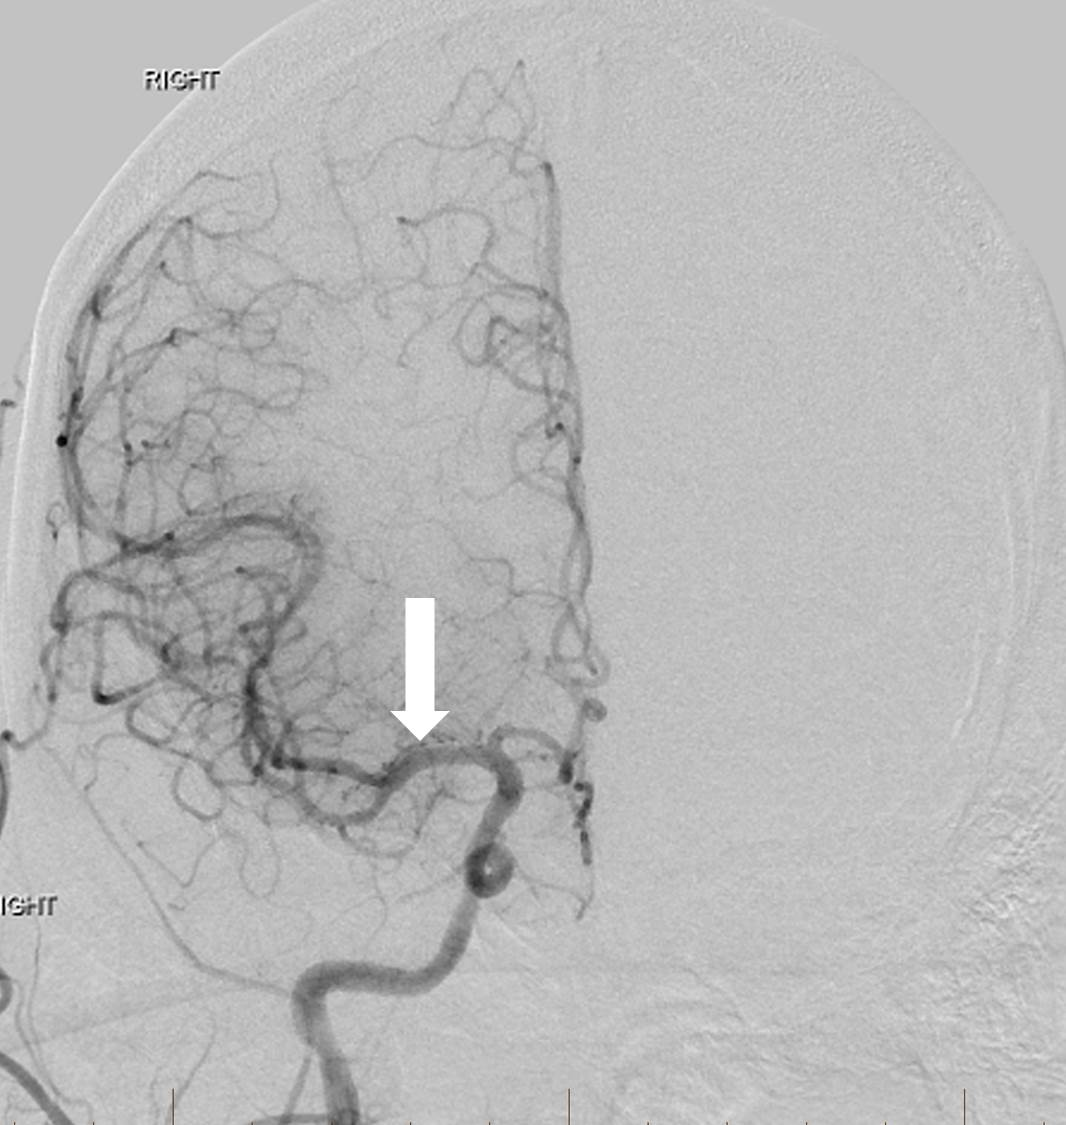

A 63-year-old man with a history of hypertension, hyperlipidemia, peripheral artery disease, smoking, and Stage IV lung cancer presented with left-sided weakness and dysarthria when he visited our institution for a chemotherapy port placement. His National Institutes of Health Stroke Scale (NIHSS) score was six and he was not a candidate for intravenous (IV) thrombolytics. Computed tomography angiography (CTA) revealed occlusion of the extracranial right internal carotid artery (ICA) and right middle cerebral artery (MCA) but no hemorrhage or large areas of acute ischemic change. Biplane digital subtraction angiography (DSA) revealed tapering to occlusion of the proximal right cervical ICA at the level of the carotid artery bulb (Figure 1).